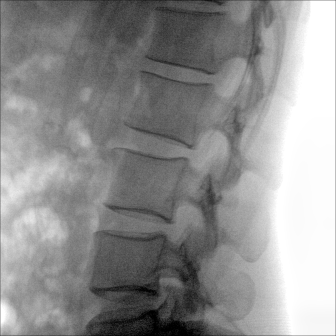

大尺寸動態(tài)平板探測器,高DQE、低噪聲、圖像清晰。采用多分辨率圖像增強處理技術(shù),不同部位不同圖像處理算法,滿足客戶多樣化的需求。

采用智能變頻脈沖透視技術(shù),優(yōu)化圖像質(zhì)量的同時降低輻射劑量,呵護醫(yī)患健康